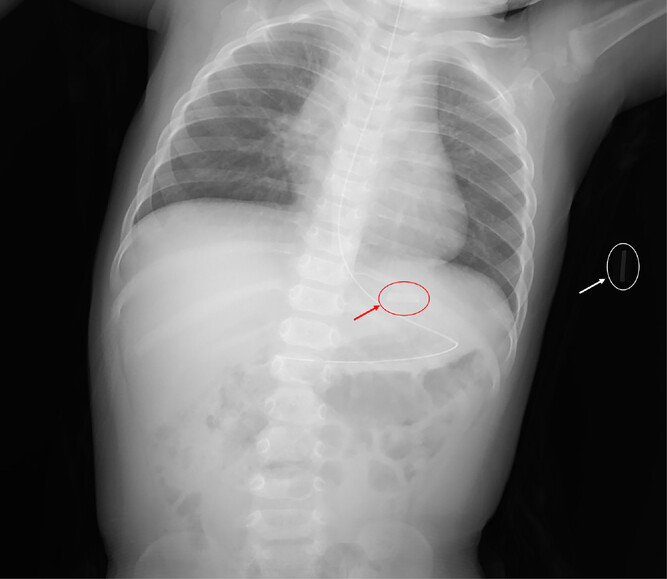

Infant with accidental ingestion of heated tobacco (2023)

onlinelibrary.wiley.com/doi/10.1002/emp2.12959